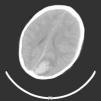

Durante su estancia en urgencias presenta disminución del nivel de consciencia, dos vómitos y tendencia a la bradicardia (50-60 lpm), sin variaciones relevantes en cifras de PA. Ante el deterioro neurológico con sospecha de hipertensión intracraneal, se inician medidas antiedema (elevación de la cabeza 30°), terapia hiperosmolar (suero salino 3%), manteniéndose estable la paciente. Se realiza una TC craneal urgente que objetiva una lesión intraaxial parietal posterior izquierda (fig. 1) de 4 × 3,1cm, de alta atenuación, con áreas heterogéneas de menor atenuación en su interior y rodeada de un moderado halo de edema en relación con la hemorragia parenquimatosa, con posible lesión subyacente, que ejerce efecto masa con herniación subfalciana y transtentorial; acompañada de un hematoma subdural frontoparietotemporal izquierdo.